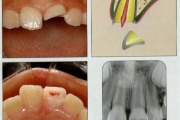

Trauma klassifikatsioon 2 (Mitsuhiro Tsukiboshi,DDS)